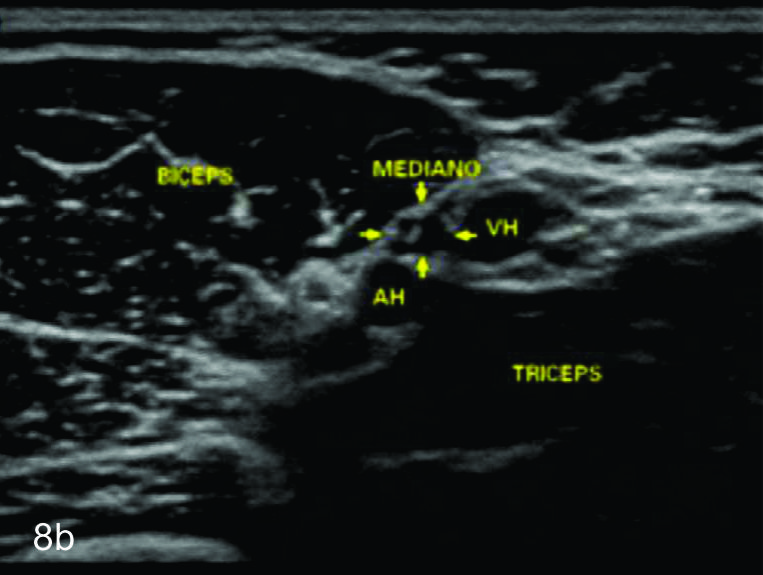

Figura 8

Nervio mediano

Serie de cortes axiales del nervio mediano desde su origen a nivel del hueco axilar hasta el sector distal del antebrazo previo a su ingreso al túnel del carpo. Se identifica el mismo señalado por flechas amarillas y con la palabra mediano. AA-arteria axilar, VA- vena axilar, AH- arteria humeral, VH- vena humeral, VB- vena basilar, AC- ateria cubital, VC- vena cubital, BA- músculo braquial anterior, PR- músculo pronador cuadrado, FS- músculo flexos superficial, FP- músculo flexor profundo, PC- músculo pronador cuadrado. A- axila, se identifica el nervio superfical a la arteria axilar, B- tercio medio del brazo en canal bicipital medial, lateral a la arteria humeral, C- codo, medial al tendón distal del bíceps braquial y a la arteria humeral luego de cruzarla, superficial al músculo braquial anterior, D-antebrazo sector cefálico, entre las dos cabezas del pronador redondo, E- tercio medio del antebrazo, entre los músculos flexor superficial y profundo F- tercio distal antebrazo, superficial al pronador cuadrado.